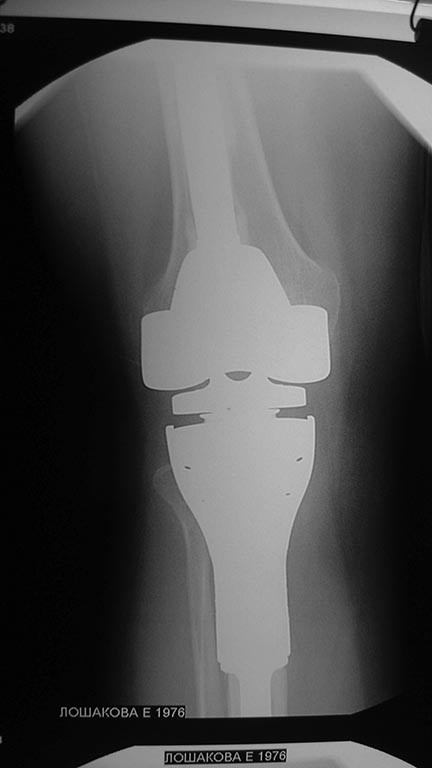

ка1кч432Уважаемые коллеги помогите с дальнейшей тактикой лечения.Больная

1976 г.р оперирована в октябре 2012 по поводу остеобластокластомы

проксимального метафиза пр.большеберцовой кости модульным имплантом

stryker послеоперационное течение гладкое.Ходит с полной

нагрузкой.Незначительно прихрамывая на пр.ногу .П/о рубец до 20 см без

признаков воспаления Пальпаторно по передней поверхности метаэпифиза

ю/берцовой кости .Активного разгибания нет ,и собственная связка

надколенника не контурирует.Пассивные движения в полном обьеме.На

контрольных рентгенограммах признаков нестабильности нет.В течении

последних трех недель появилось по передней поверхности пр.голени

серома.Пунктирована несколько раз– прозрачная синовиальная

жидкость.Взята на посев–чуствительна к гентомицину,цефазолину

,цефтриаксону и левофлоксацину.В настоящее время получает цефазолин 1.0

в/м 3 раза и гентомицин 160 мг в/м 1 раз.(уже 5 дней)Динамики нет,

жидкость продолжает скапливаться примерно в том же обьёме.